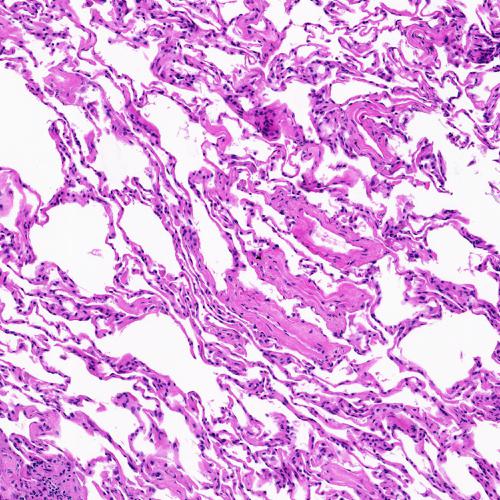

Dataset and Data Preparation – We used the KimiaPath24 dataset to evaluate our experiments. This dataset contain 24 WSIs. The slides show diverse organs and tissue types with different texture patterns [5]. The glass slides were captured by a digital scanner in bright field using a 0.75 NA lens 111TissueScope LE scanner by Huron Digital Pathology. The dataset contains 1325 test images (patches) of size 1000 1000 pixels (0.5mm 0.5mm) from all 24 cases. Fig. 1 shows some example patches (the dataset can be downloaded online222http://kimia.uwaterloo.ca/kimia_lab_data_Path24.html).

All training and test patches are down-sampled from pixels to pixels in order to be more easily processed by for the feature extraction. We patched WSIs without overlap and then we removed all patches with high background homogeneity (more than ) [5]. As a result, we created 27,055 training patches from 24 WSIs. The presented dataset comprising of diverse body parts may be suitable for intra-class search operations such as metastasis and floater detection.